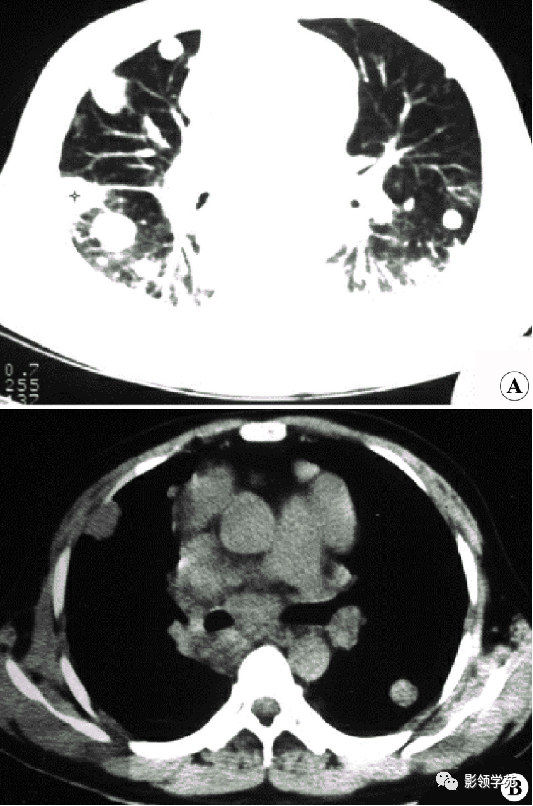

肺转移瘤。肺窗像(A)示双肺野可见大小不等的圆形高密度结节影,纵隔增宽;纵隔窗像(B)示肺内肿块呈实性,纵隔满布大小不等的肿大淋巴结

CT诊断:甲状腺癌双肺多发转移